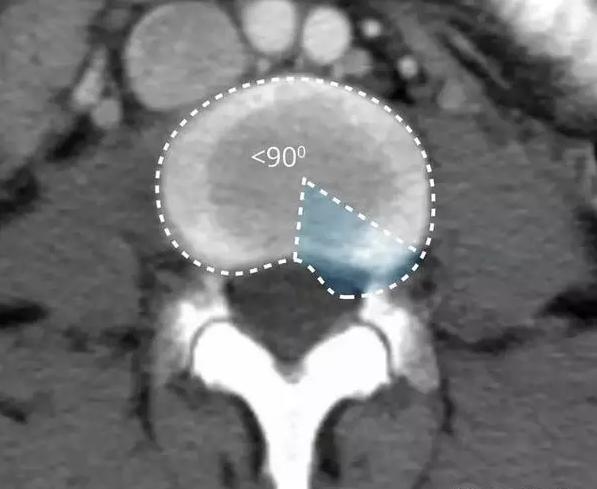

病情进一步进展,纤维环破裂了,髓核由于是胶状物在压力作用下就从破口处挤压了出来,这时候就是椎间盘的突出!

在影像学上表现为椎间盘局限性向椎管内突出。